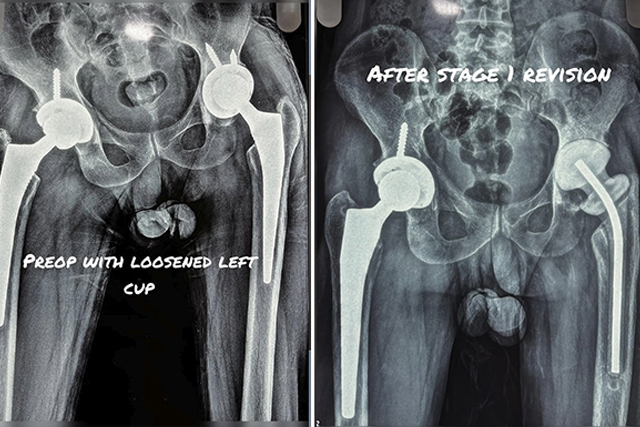

Two-Stage Revision Hip Replacement